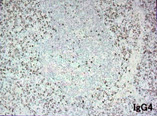

胚中心を伴うリンパ濾胞が散在し濾胞間に形質細胞が密に集簇して認められる。形質細胞系細胞はIgG陽性でkappa, lambda染色よりpolyclonalと考えられた。IgG陽性細胞の60-70%はIgG4陽性。リンパ濾胞内にIgG4産生細胞が散在していた。

IgG4